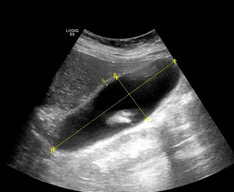

Abdominal CT scan. Visible presence of varices at the hilum of the spleen (Courtesy Dr. V. Penopoulos)